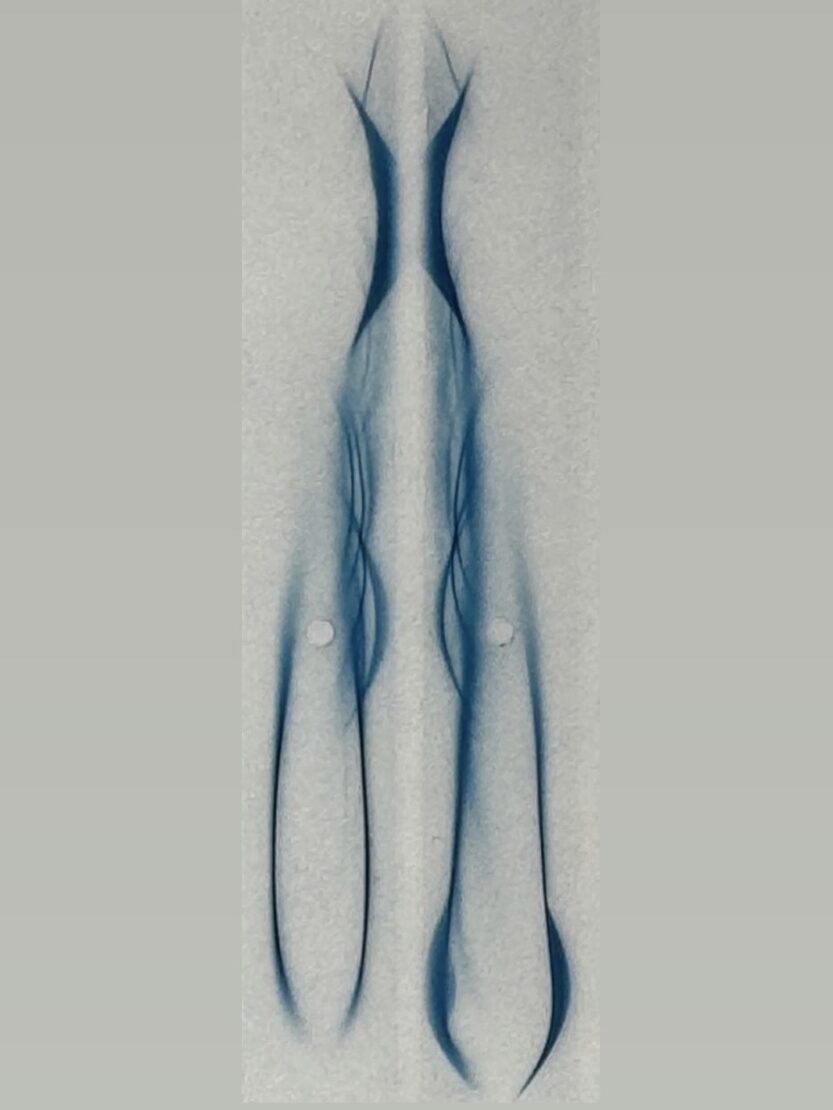

🔹免疫電気泳動法

血液中のたんぱく質を電気の力で移動させ、成分ごとに分けたあと抗体と反応させます。

たんぱく質の分布やバランスを調べる基本的な検査法です⚡